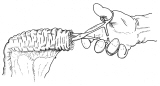

器械吻合器テクニックあれこれ

あのころ、実用化されたばかりの自動吻合器の使用上の「コツ」シリーズ。